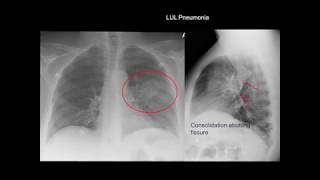

o nódulo vidro fosco e vidro fosco e que parece está consolidando aqui no meio que que é isso bom gente existem vários tipos de nódulos e quando o nosso é todo sólido quando é todo sólidos ele aparece opa ele aparece branco é um como você tá vindo aqui inclusive aqui tem até umas especulações minhas né esse aqui não tá muito gatinho nós aqui tá mais eu esse aqui tá na Malícia tá jogando na Malícia esse aqui mas se o nódulo não fosse sólido se ele for semi ou se ele não for sólido pronto totalmente não

sólido ele vai aparecer como vidro fosco Então quando você vir um vidro fosco muito redondo no paciente cuidado com simplesmente atribuir aquilo uma infecção e acabou viu o vidro fosco muito Redondo pode ser um nódulo não só lhe e o vidro fosco muito Redondo mas que no meio tem consolidação espécie de consolidação Mais logo Lar isso pode ser um nódulo sem só lhe tá The Sims óleo vai ter um componente denso do país óleo em um componente de vidro fosco da parte não só lhe sem sódio bom então cuidado muito cuidado porque um dos recursos